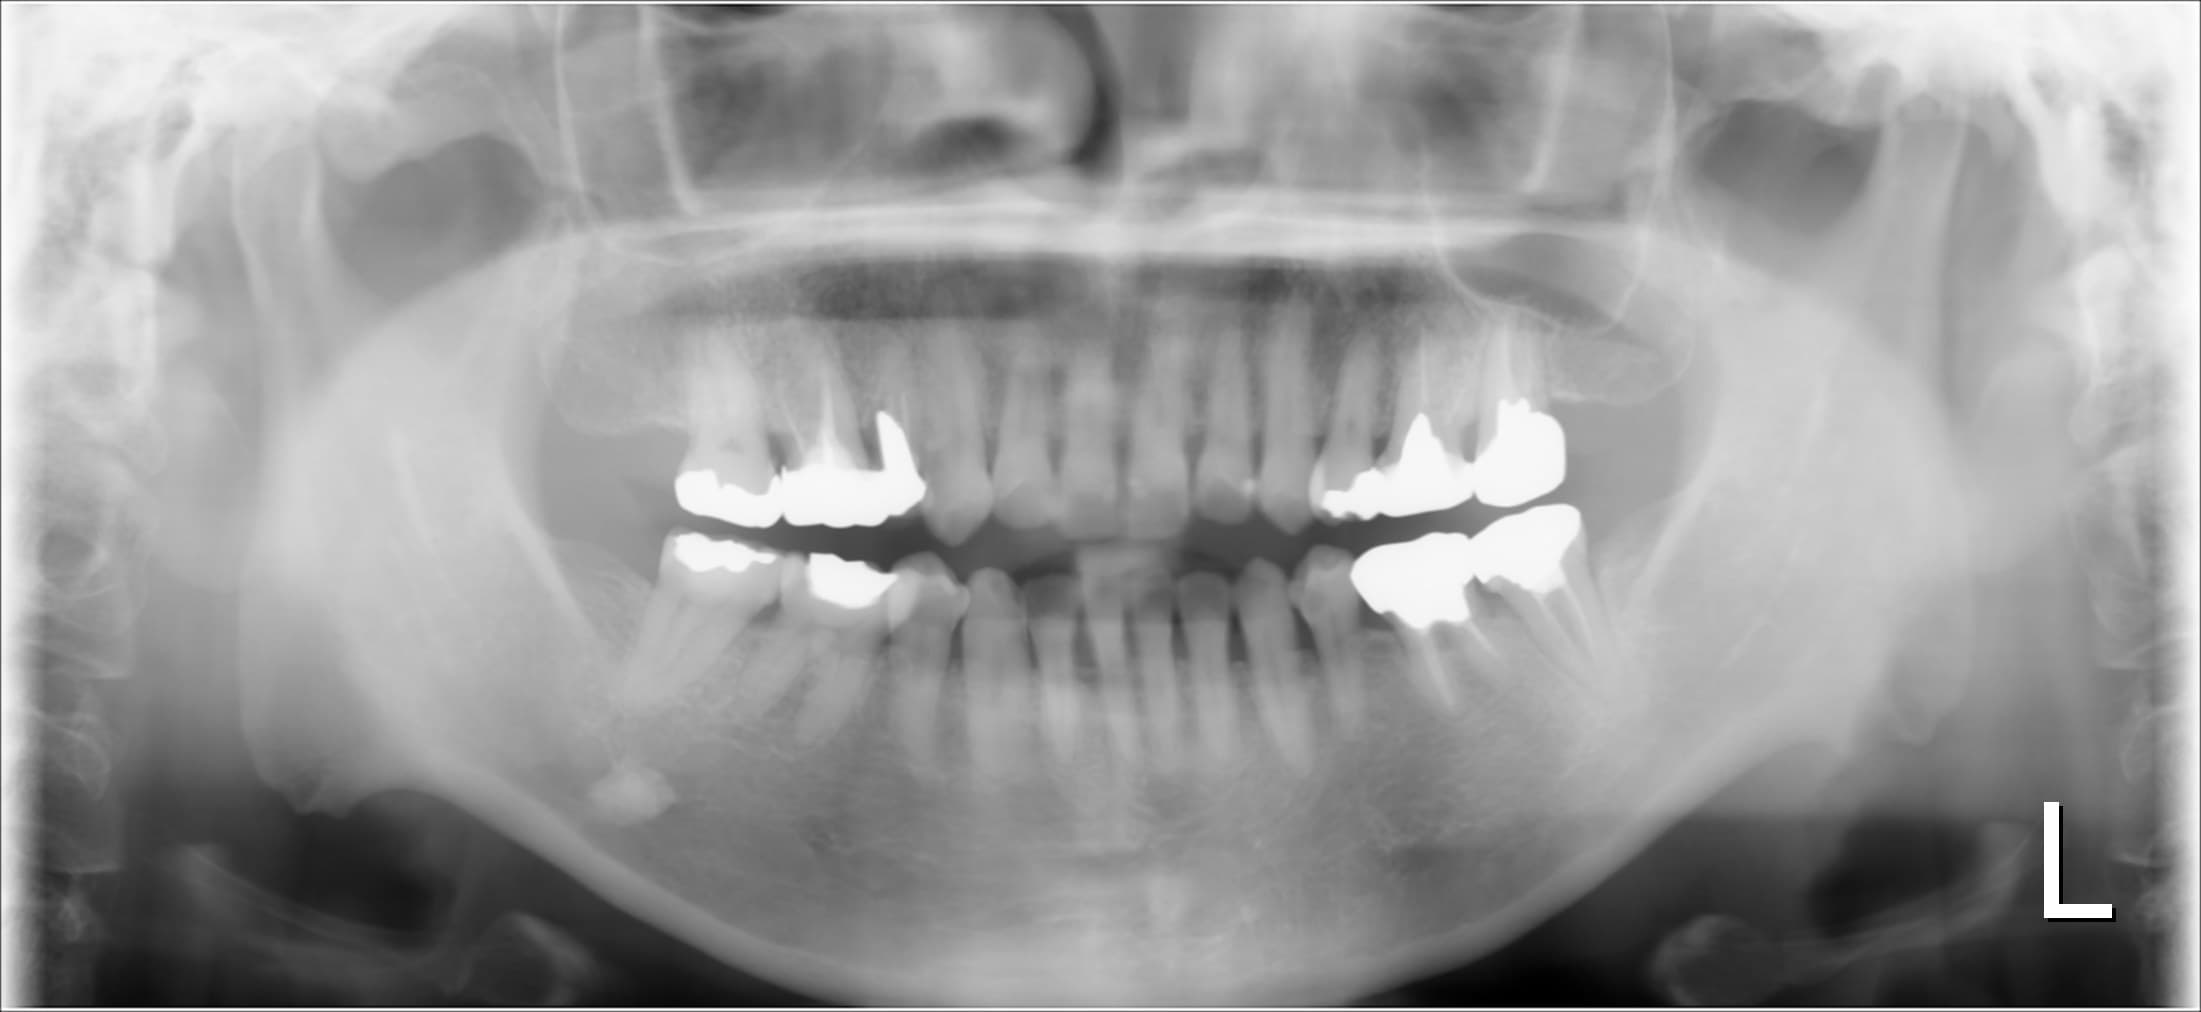

今回ご紹介する歯周専門治療のケースは、60代女性の方です。

50代から長期間身体を壊し、他院にて6か月に1度歯石取り(メンテナンス?)を行っていましたが、一向に口腔内のネバネバや不快感が改善しなかった為、来院されました。

基本検査の結果、全体的に中程度の歯周ポケットがあり、歯肉からの出血、歯周ポケット内に歯石を確認することができました。

またお手入れは、ご自身では見え難いところに磨き残しがありました。

治療前

口腔内のネバネバや不快感といった症状は、全身的な疾患も影響する場合もあるので、残念ながら歯周基本検査だけで断定できません。しかし検査の結果、その方に歯周病があれば、原因の一つとなり得るので、歯周病のコントロール行っていく必要があります。